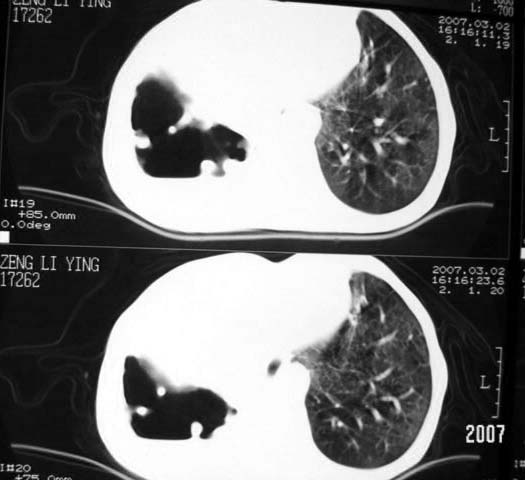

以下是引用dyqct在2007-3-2 22:04:00的发言:[br]考虑:1、右侧毁损肺伴支气管胸膜瘘(多条支气管与胸腔相通、液气胸);[br] 2、左肺浸润型肺结核。[br][br][br][br]